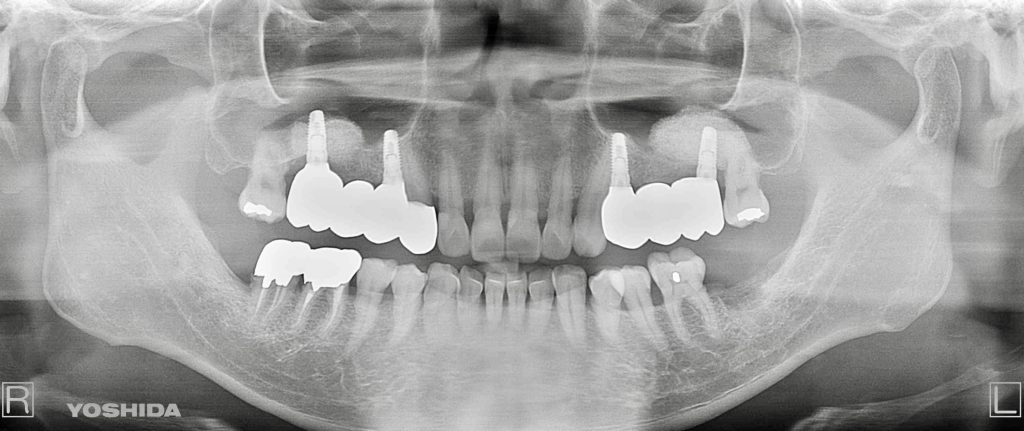

下記の症例は上顎臼歯部(上の奥歯)の骨量が不足している症例に対し、難易度の高いサイナスリフトを行い、骨量を改善させたのちインプラント埋入を行いました。